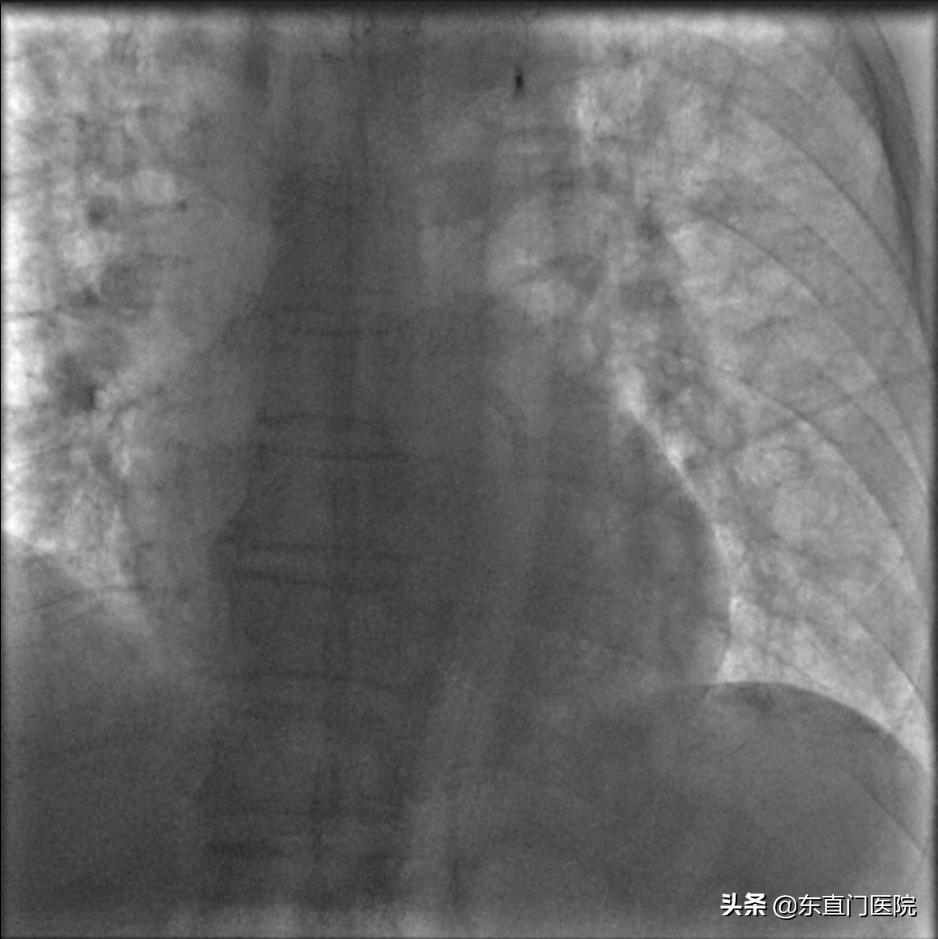

患者接受IABP治疗 |

IABP影像 |

复苏成功后,为最大程度提高患者生存率,紧急穿刺右股动脉,于患者主动脉内置入了主动脉内球囊反搏(Intra Aortic Balloon Pump,IABP)装置,并经右股静脉穿刺建立中心静脉抢救通道;